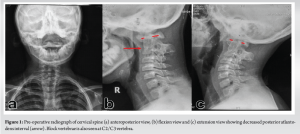

A 14-year-old boy presented to the spine clinic with progressive weakness of the bilateral upper limb, progressing to bilateral lower limb for the past 1.5 years following trivial trauma to the neck and with bowel and bladder incontinence for the past 1 year. At presentation, he was not able to stand without support, had increased tone (modified Ashworth grade 1) in bilateral upper and lower limbs, with functional motor power present and no sensory deficit in any of the dermatomes. On elicitation, both upper and lower limb reflexes were exaggerated. Exaggerated pectoralis reflex and presence of scapulohumeral reflex suggested a clinical diagnosis of supra-axial cervical myelopathy. On further evaluation, special signs such as Hoffman’s sign and grasp-release test were positive. Cervical spine radiograph showed atlantoaxial subluxation with decreased posterior atlanto-dens interval along with fusion of C2 and C3 vertebrae (Fig. 1). On magnetic resonance imaging cervical spine, thecal sac and spinal cord compression at the level of C1/C2 joint with no visible cerebrospinal fluid rim was noted (Fig. 2). 3D Computed tomography angiography (CTA) of the cervical spine showed an incomplete anterior and posterior arch of the atlas with well-corticated bony fragments within the posterior arch defect. Note of fenestration of VA on right side and high-riding VA was also made (Fig. 3). A final diagnosis of supra-axial extradural compressive cervical myelopathy due to congenital atlantoaxial subluxation with anomalous VA (Nurick Grade 5) was made. The patient was planned for C1-C2 reduction and posterior instrumented fusion using C1 lateral mass and C2 laminar screws under intraoperative neuromonitoring. The patient was positioned prone on Mayfield, and a longitudinal midline approach from C1 to C3 was carried out, elevating the paraspinal muscle subperiosteally from the midline. A congenital defect in the posterior arch of C1 was noted. First, the left side C1 lateral mass screw was put after identifying the entry point. On the right side, the aberrant VA was freed from the posterior arch of C1 and retracted, inferiorly exposing the lateral mass of C1 along with facets of C1-C2 joint, and C1 lateral mass screw was inserted. Further, laminar screws were placed bilaterally in C2. C1 was reduced over C2 using rod cantilever mechanism and by applying compression force bilaterally between the C1 lateral mass and the C2 laminar screws. Decompression was achieved by removing the remaining C1 posterior arch and corticated bony fragment from the midline. Harvested local bone autograft was placed in the C1-C2 joint on the left side and the prepared fusion bed posteriorly (Figs. 4 and 5).